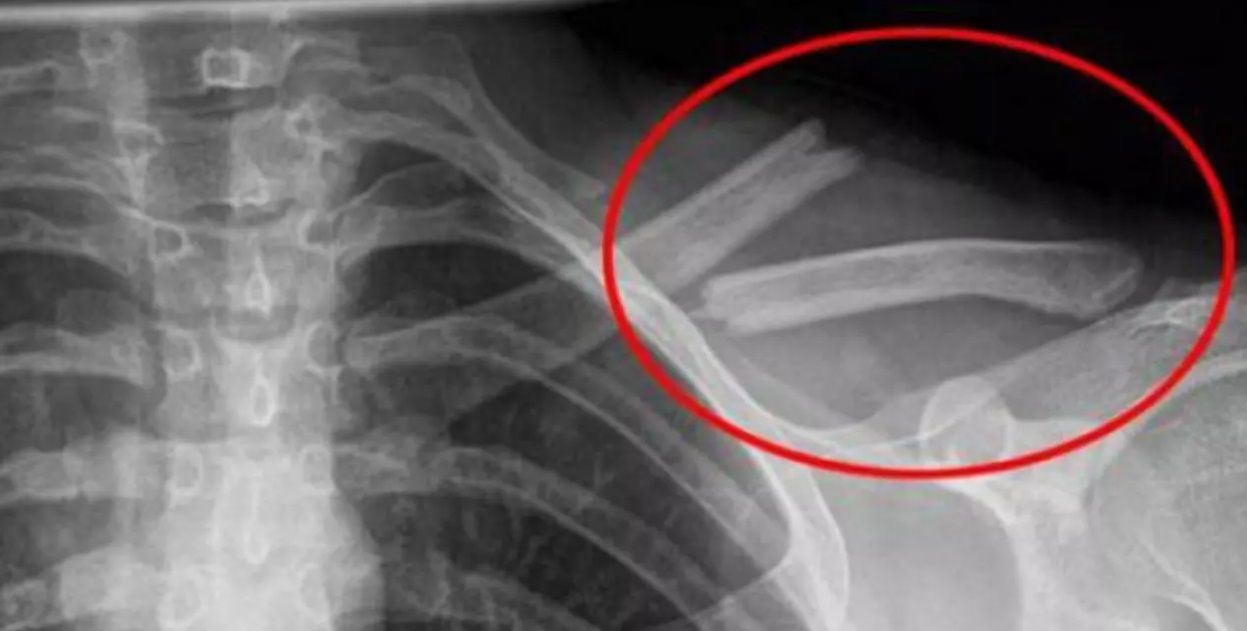

Osteoporoza după 45 de ani: Cum te ajută calciul, vitamina D și sportul să previi fracturile de Alecu Carmen Publicat: 30 martie 2025 11:30